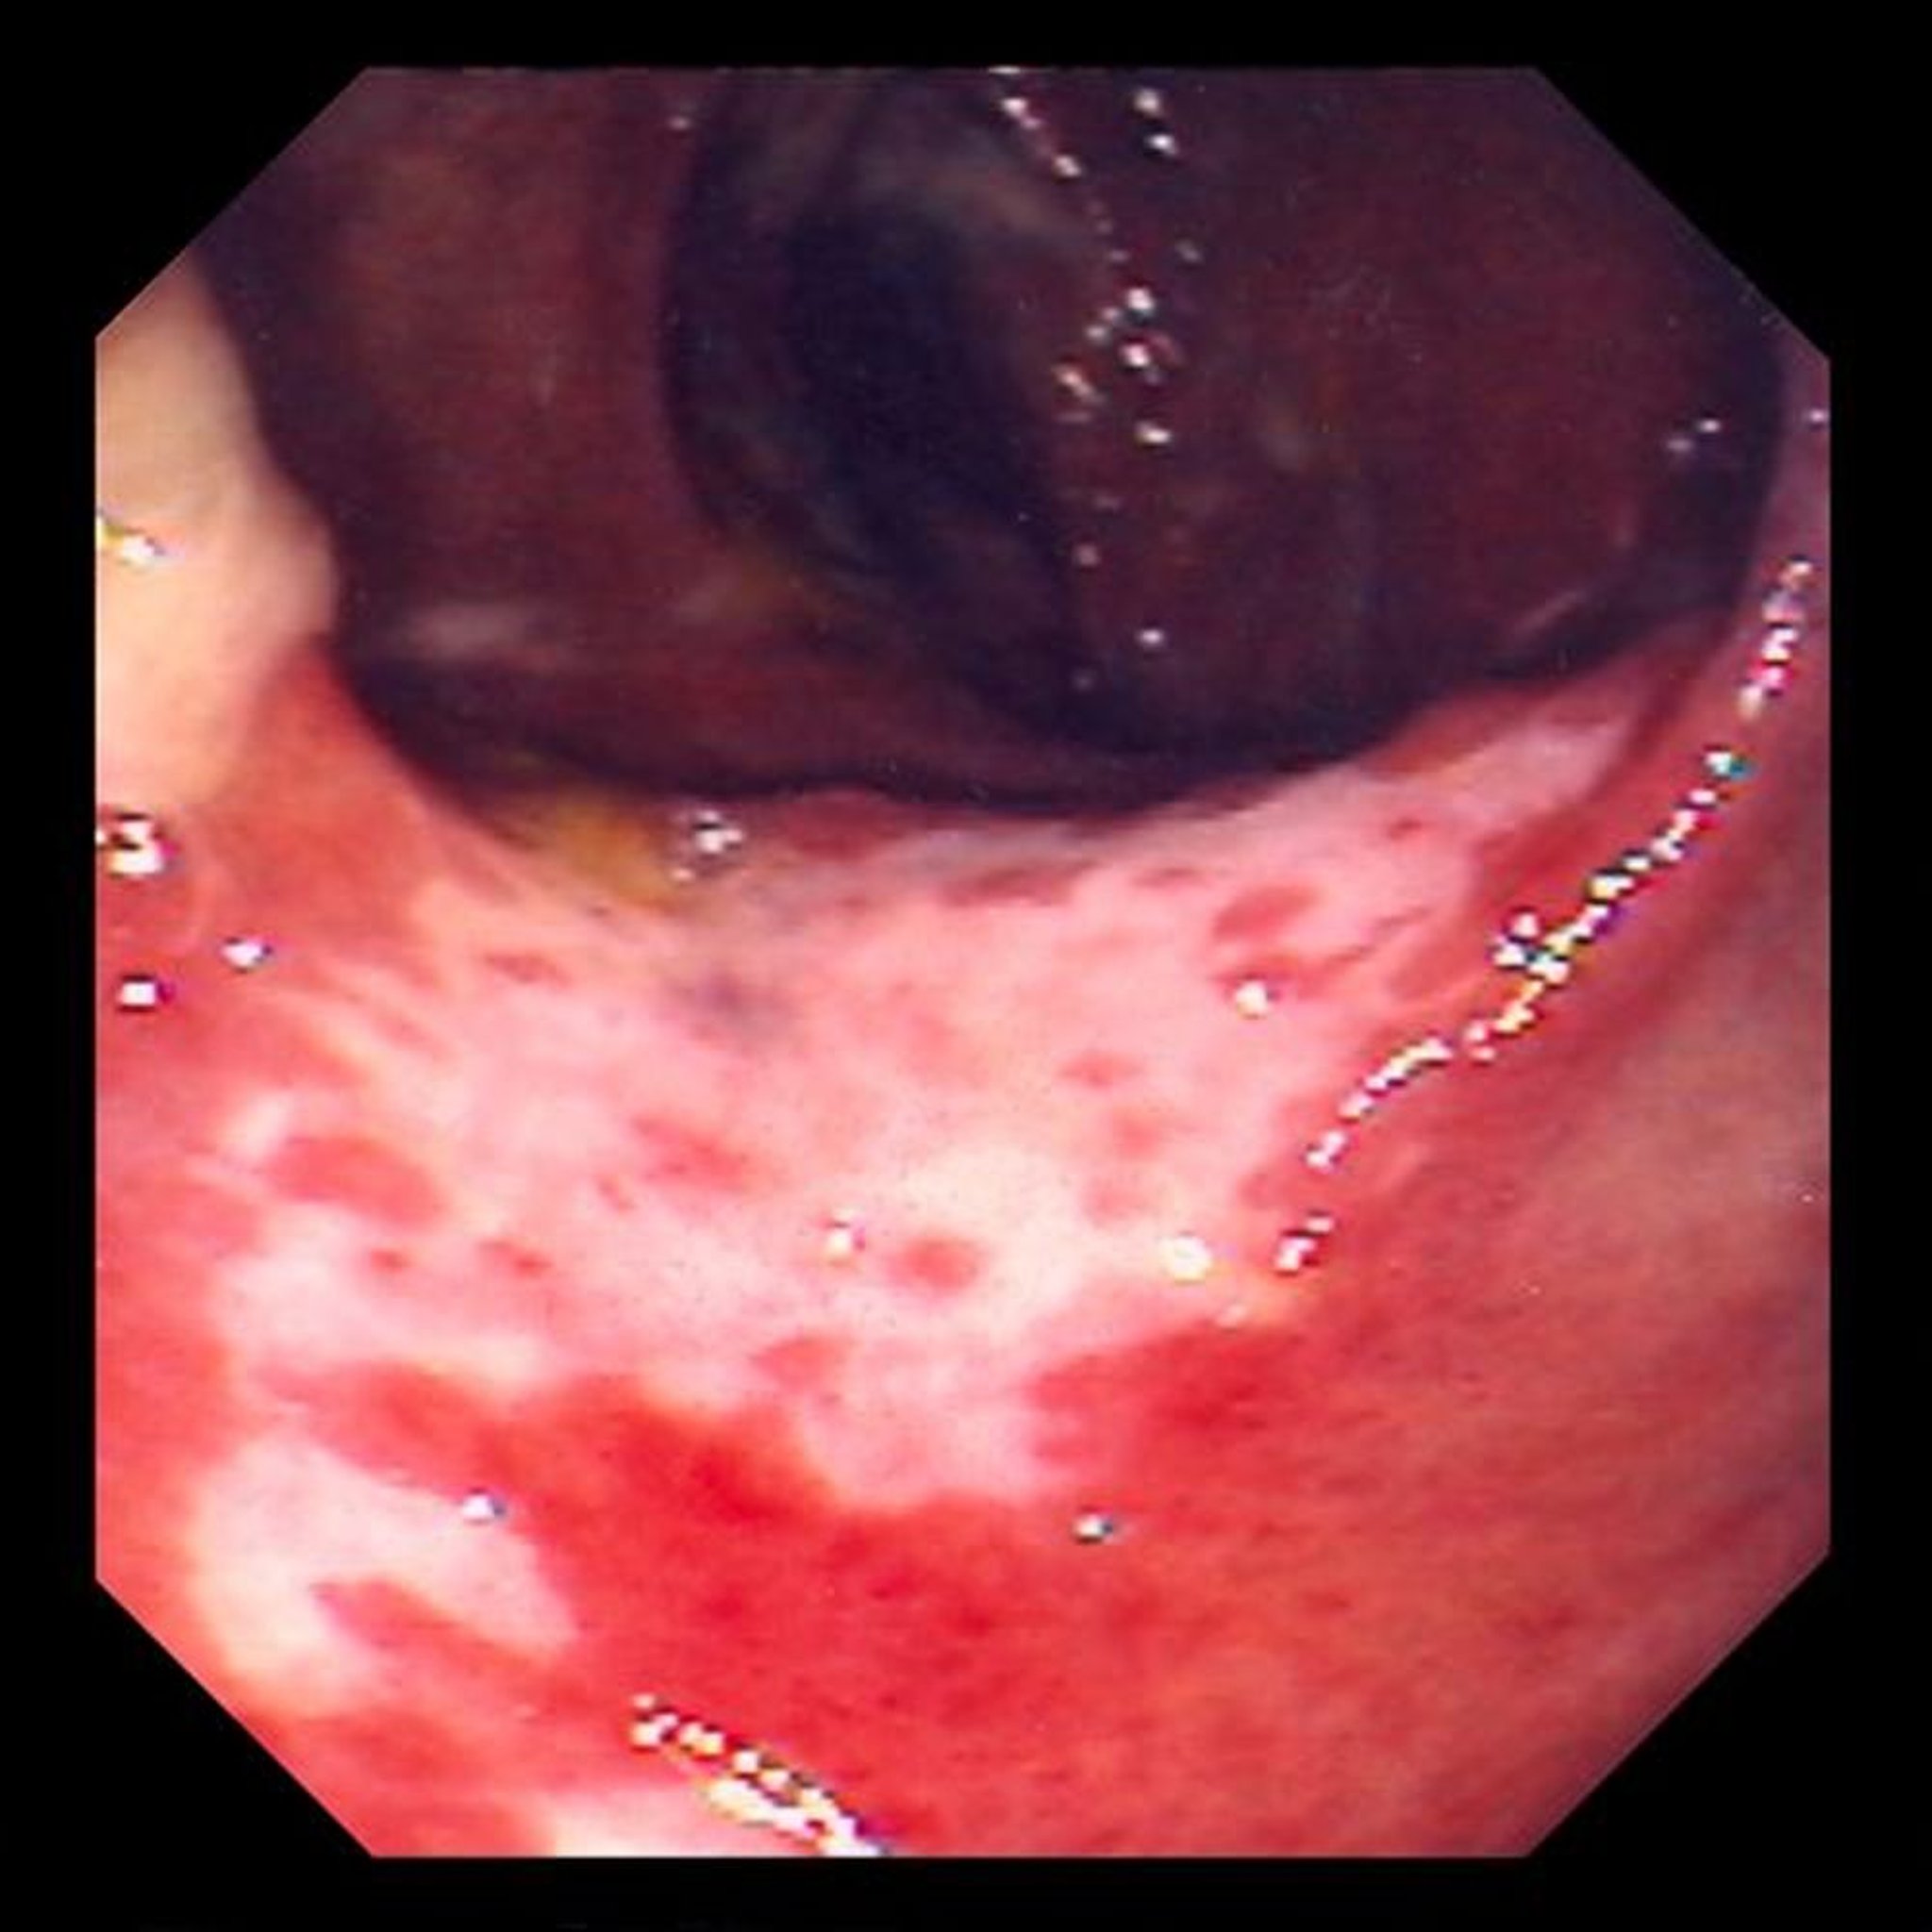

Ишемический колит (колоноскопия)

На данной фотографии изображено повреждение слизистой оболочки кишечника, вызванное закупоркой кровотока. Слизистая оболочка кишечника имеет красный цвет и покрыта язвами (белые области).

Фотография предоставлена д-ром Дэвидом М. Мартином (David M. Martin, MD).